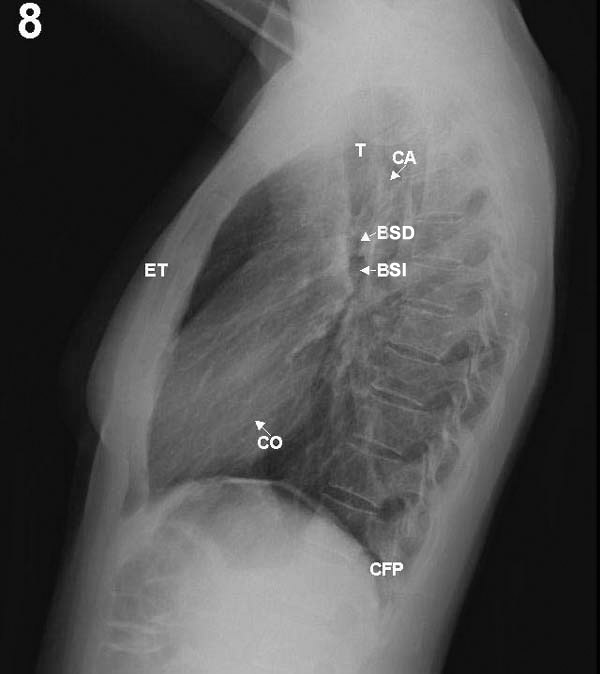

Pase primero a la placa 7 (frontal) y localice en ella las marcas correspondientes

a los elementos que a continuación se indican. Después haga lo

mismo con la placa lateral 8.

PLACAS 7 Y 8

detrás del corazón. En la proyección lateral las

vértebras se ven más claramente, viéndose más

blancas las superiores por la sobreposición de las masas musculares

de la cintura escapular.

ESTERNON: se ve en su totalidad en la proyección lateral

(ET), mientras que en frontal sólo se ve la zona del manubrio por

encima de la extremidad de la segunda costilla. Ocasionalmente puede aparentar

un ensanchamiento de la parte alta del mediastino.

infrapulmonar al lado izquierdo. En esta última proyección

puede apreciarse que, por tener las inserciones posteriores del diafragma

una posición más caudal, los senos costofrénicos

posteriores (CFP), están situados varios centímetros por

debajo de los anteriores y laterales y son los primeros que se borran

al iniciarse un derrame pleural..

TRAQUEA: en la placa frontal se ve como una tenue columna aérea

a la derecha a nivel del cayado aórtico. En la radiografía

lateral es levemente oblicua de delante a atrás.

En proyección lateral, estos bronquios principales se superponen

y no son diferenciables, pero las ramas para los lóbulos superiores

de ambos pulmones (BSD y BSI) siguen un trayecto horizontal, relativamente

paralelo al haz de rayos, por lo que sus paredes son atravesadas longitudinalmente

y contrastan como claridades redondeadas superpuestas al eje traqueal,

siendo la más alta la correspondiente al bronquio derecho. Las

En la placa lateral la sombra cardíaca descansa y se confunde con

la mitad anterior del hemidiafragma izquierdo. Su borde anterior está

formado por el ventrículo derecho (VD) y el posterior por la aurícula

izquierda arriba, el ventrículo al medio y la vena cava inferior,

abajo. El cayado aórtico (CA) puede distinguirse parcialmente como

un arco anteroposterior.

en que los rayos la atraviesan tangencialmente. La cisura menor u horizontal

del lado derecho se ve frecuentemente en la radiografía frontal

y casi siempre en la lateral. Las cisuras mayores u oblicuas (CO) no son

apreciables en la placa frontal, pero suelen verse en la lateral como

finas líneas oblicuas de atrás a adelante y de arriba a

abajo.